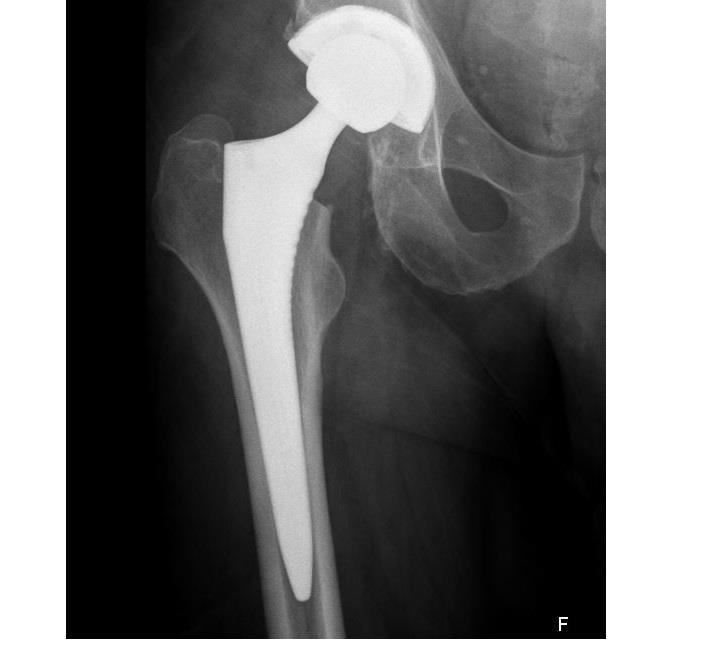

בניתוחי החלפת מפרק הירך מוחלפים שני צדי המפרק במשתלים מלאכותיים: בצד עצם האגן מושם משתל בצורה כיפה קעורה ("המכתש") ובצד עצם הירך משתל קמור ("תפוח").התנועה הסיבובית של המפרק נוצרת בין המכתש לתפוח.באזור המפרק בין המכתש לתפוח ישנן אפשרויות לשימוש בחומרים שונים. כולם טובים, אך לכולם גם יתרונות וחסרונות שכדאי להכיר על מנת לבחור באופן מושכל את המתאים ביותר.

4. כיצד מקבעים את המשתלים לעצמות?

משתל ללא צמנט ייצמד בשלב הראשון בחוזקה ובאופן מכני לעצם (בשל התאמה מיטבית של שלו לאנטומיית המטופל וחיתוך מדויק של העצם), אך תוך מספר שבועות העצם תצמח ותגדל לתוך פני השטח המחוספסים של המשתל כך שיהוו יחידה אחת והמשכית, או במילים פשוטות יותר ייווצר קיבוע ביולוגי.